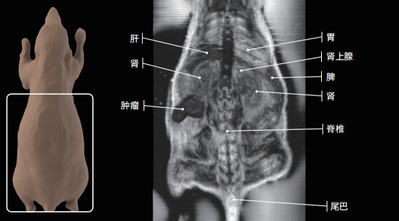

3.小动物核磁共振成像系统

小动物核磁共振成像系统

名称:小动物核磁共振成像系统

品牌:纽迈科技

型号:M5

产地:中国上海

技术特点:

■采用永磁体设计,具有高性能、高灵敏度的射频线圈和用户友好的应用软件,软件支持层数、层厚、FOV等多参数调节,可提供高质量的磁共振图像。

■配备专业高性能工作站电脑,内置专业操作软件,可为用户提供多种高级采集模式和分析方法。

■配置生理监控系统,准确测量动物体温、呼吸等生理数据。 配置小动物专用MRI成像床,与主机、生理监控系统整合,可实现小动物的固定、定位、加热和生理监控。

■小动物磁共振图像软组织对比度好:主要应用于检测实体脏器,如脑、心脏、肝脏、肾脏、肌肉等。

主要功能:

主要用于小鼠、大鼠的活体成像研究,可提供啮齿动物和离体样本的无创3D解剖和功能性结果。该设备具有无电离辐射、无骨性伪影、多参数成像等优势,能够在不破坏样品的情况下实现快速无损检测。

应用领域:

其应用涵盖肿瘤学、神经生物学、心血管疾病等领域,支持造影剂评价、药物作用分析及全身脂肪分布成像等科研功能。

肿瘤研究: 评估药物作用及肿瘤组织成像。

神经生物学: 脑梗模型、脑肿瘤及颅内动脉瘤研究。

心血管疾病: 血管结构显示。

代谢研究: 小动物脂肪分布成像。